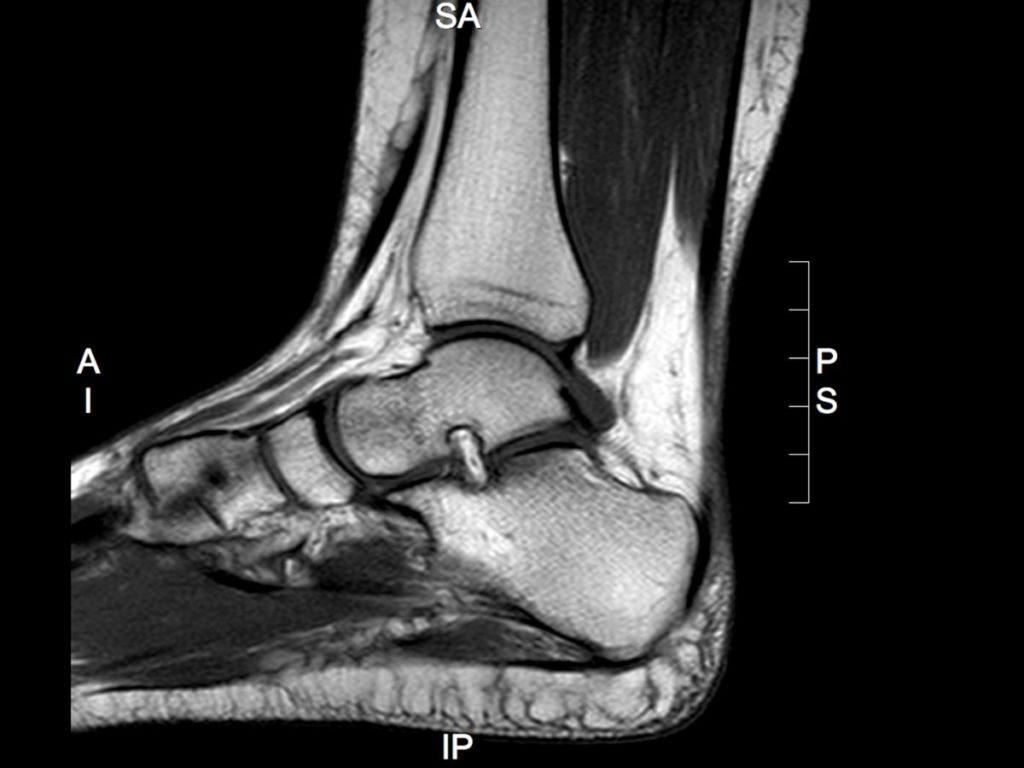

Foot and ankle pain is often attributed to local musculoskeletal pathology; however, clinicians should remain alert to the possibility of underlying systemic or metabolic causes. […]